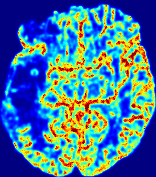

LesionRefer to captionRefer to captionRefer to captionRefer to captionRefer to captionRefer to caption𝐕rgbsubscript𝐕𝑟𝑔𝑏{\bf{V}}_{rgb}Refer to captionRefer to captionRefer to captionRefer to captionRefer to captionRefer to caption𝐕2subscriptnorm𝐕2{\|\bf{V}}\|_{2}Refer to captionRefer to captionRefer to captionRefer to captionRefer to captionRefer to captionRefer to caption3.53.53.52.82.82.82.12.12.11.41.41.40.70.70.70.00.00.0(mm/s)𝑚𝑚𝑠(mm/s)D𝐷DRefer to captionRefer to captionRefer to captionRefer to captionRefer to captionRefer to captionRefer to caption0.0200.0200.0200.0160.0160.0160.0120.0120.0120.0080.0080.0080.0040.0040.0040.0000.0000.000(mm2/s)𝑚superscript𝑚2𝑠(mm^{2}/s)Slice #1Slice #2Slice #3Slice #4Slice #5Slice #6

Figure 3: PIANO feature maps for one stroke patient, where the lesion is located in the left hemisphere. Top row: segmented stroke lesion region (white) on different slices, obtained from ISLES 2017. The corresponding slices for the PIANO feature maps are shown in the following rows.

For a better insight into an estimated velocity field 𝐕𝐕{\bf{V}} and diffusion field 𝐃𝐃{\bf{D}}, we compute the following maps: (1) 𝐕rgbsubscript𝐕𝑟𝑔𝑏{\bf{V}}_{rgb}: Color-coded orientation map of 𝐕=(Vx,Vy,Vz)T𝐕superscriptsuperscript𝑉𝑥superscript𝑉𝑦superscript𝑉𝑧𝑇{\bf{V}}=(V^{x},V^{y},V^{z})^{T}, obtained by normalizing 𝐕𝐕{\bf{V}} to unit length and mapping its 3 components to red, green, blue respectively; (2) 𝐕2subscriptnorm𝐕2\|{\bf{V}}\|_{2}: 222 norm of 𝐕𝐕{\bf{V}}; (3) D𝐷D: scalar field in Eq. 5.

Fig. 3 and Fig. 4 show the PIANO feature maps estimated from two ISLES 2017 patients: all are highly consistent with the lesion in both cases. Details of the blood flow trajectories are revealed in 𝐕rgbsubscript𝐕𝑟𝑔𝑏{\bf{V}}_{rgb} by the ridged patterns and the sharp changes of colors in the unaffected (right) hemisphere, while the flat patterns appearing within the lesion provide little directional information about the velocity and indicate low velocity magnitudes. Velocity magnitudes are more directly visualized via 𝐕2subscriptnorm𝐕2\|{\bf{V}}\|_{2}, from which one can easily locate the lesion where 𝐕2subscriptnorm𝐕2\|{\bf{V}}\|_{2} is low. D𝐷D also indicates lower diffusion values in the lesion, though with less contrast potentially due to the fact that it captures the accumulated effect of CA diffusion at the voxel-level.